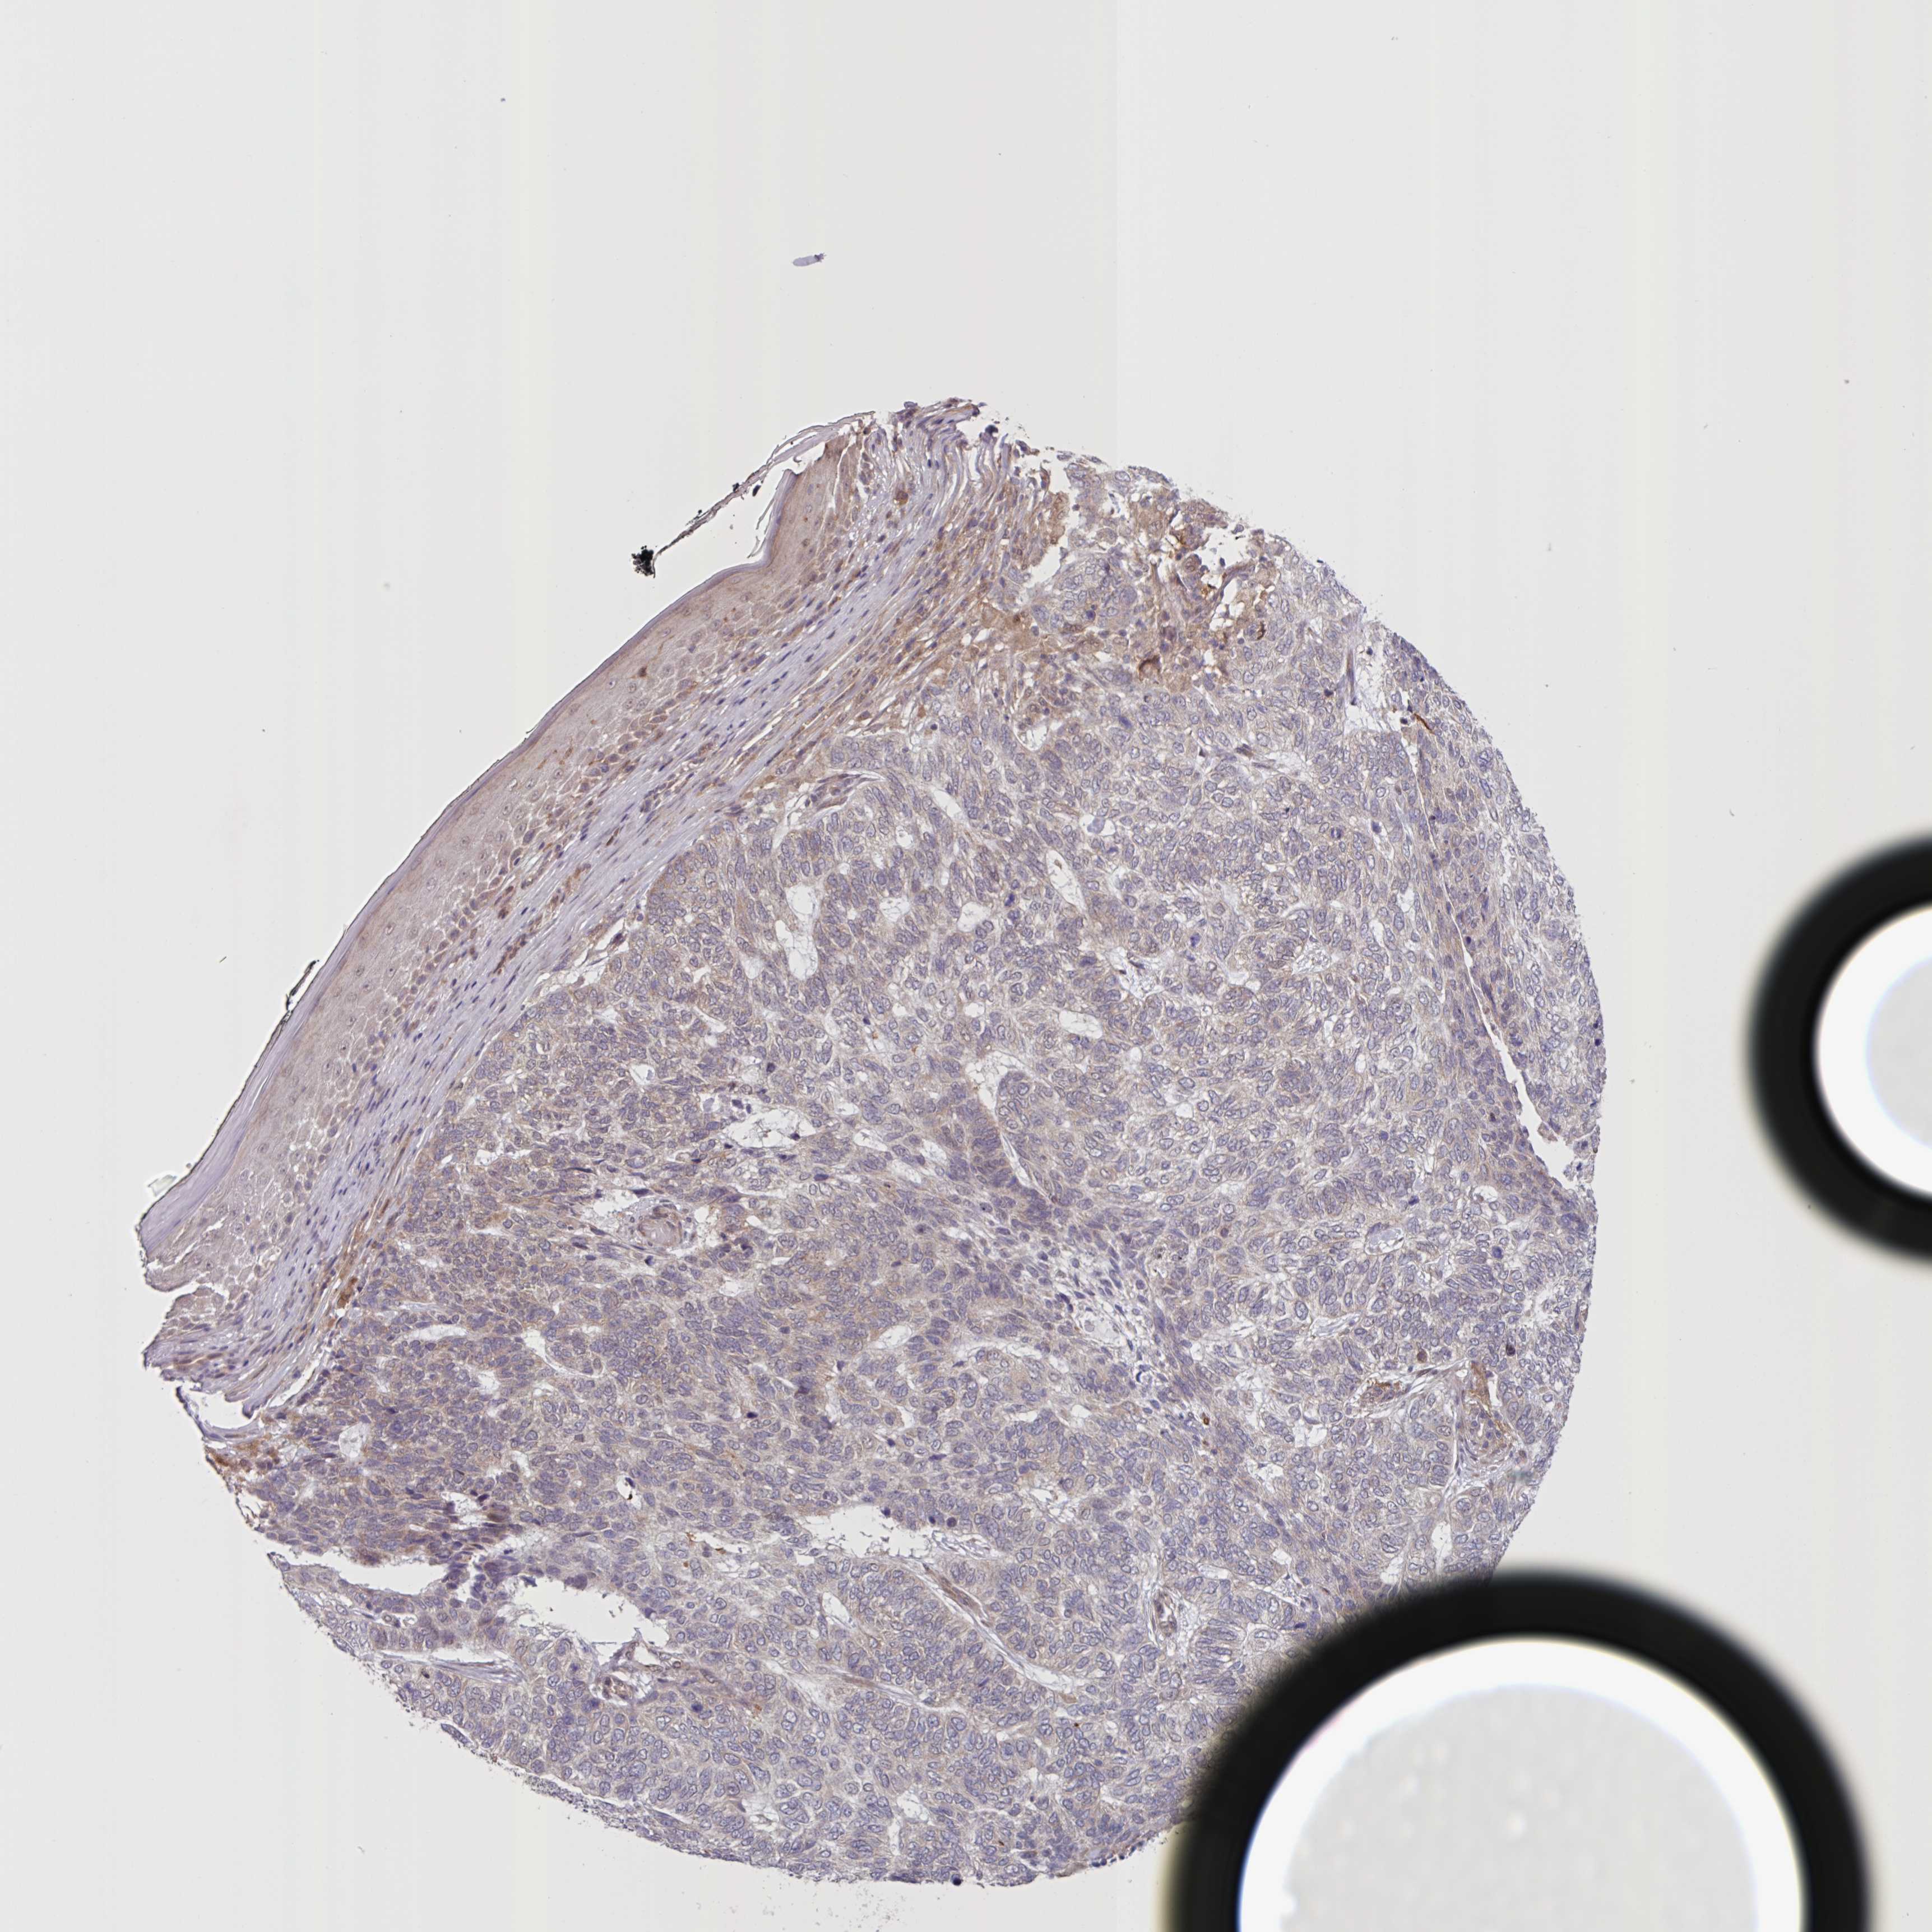

SKIN CANCER - Protein expressioni

A mouse-over function shows sample information and annotation data. Click on an image to view it in a full screen mode. Samples can be filtered based on level of antibody staining by selecting one or several of the following categories: high, medium, low and not detected. The assay and annotation is described here.

Antibody stainingi

Antibody staining in the annotated cell types in the current human tissue is reported as not detected, low, medium, or high, based on conventional immunohistochemistry profiling in selected tissues. This score is based on the combination of the staining intensity and fraction of stained cells.

Each image is clickable and will lead to virtual microscopy that enables deeper exploration of all samples and also displays staining intensity scores, fraction scores and subcellular localization as well as patient and tissue information for each sample.

Antibody HPA052636

Antibody HPA056472

Staining

High

Medium

Low

Not detected

Intensity

Strong

Moderate

Weak

Negative

Quantity

>75%

75%-25%

<25%

None

Location

Nuclear

Cytoplasmic/membranous

Cytoplasmic/membranous,nuclear

Basal cell carcinoma

Squamous cell carcinoma, NOS

Squamous cell carcinoma, metastatic, NOS